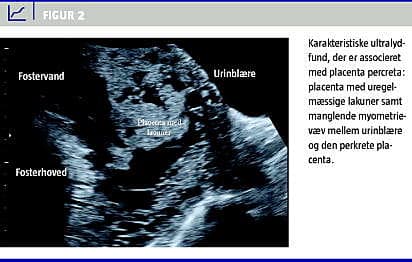

Mistanke om diagnosen PP kan rejses ved gennemskanningen i graviditetsuge 18-20 eller senere i graviditeten i forbindelse med vaginalblødning. Ultralyd (UL)- og Dopplerfund, der er associeret med PP omfatter følgende [14, 15]:

• Påvisning af store irregulære blodfyldte lakuner i placenta (Figur 2 ).

• Fravær eller abrupt ophør af den hypoekkogene retroplacentære zone, som udgør uterinvæggen bag placenta.

• Fravær af den hyperekkogene zone mellem uterus og blæren (Figur 2).

• Atypisk flow mellem placenta og det omkringliggende væv.

Irregulære lakuner i placenta er mest specifik for PP med en sensitivitet på 79-93% ved undersøgelse af højrisikograviditeter med placenta praevia eller anterior placenta og tidligere sectio [15].